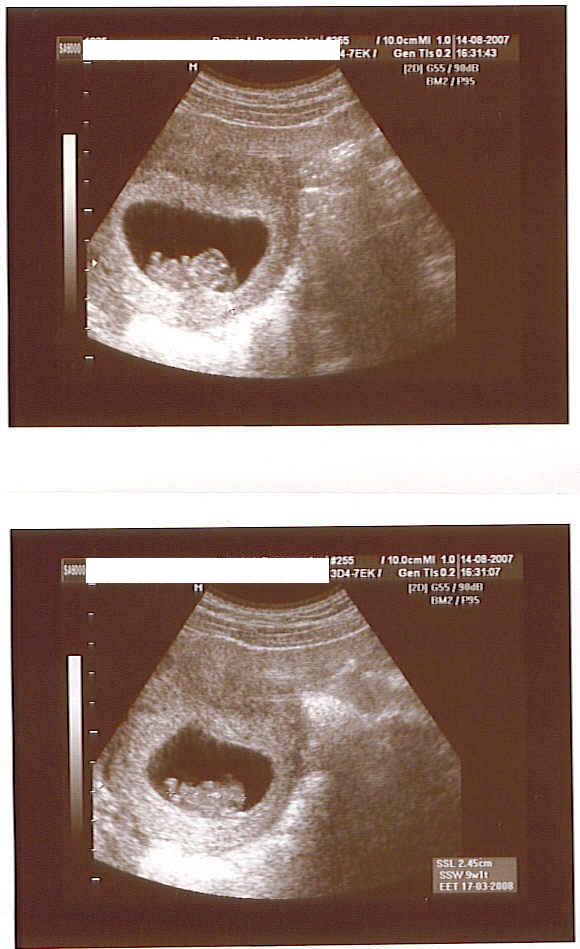

@ Kaiya: na, was macht dein Krümelchen ? Ich hoffe, dass es sich weiterhin prächtig entwickelt !!